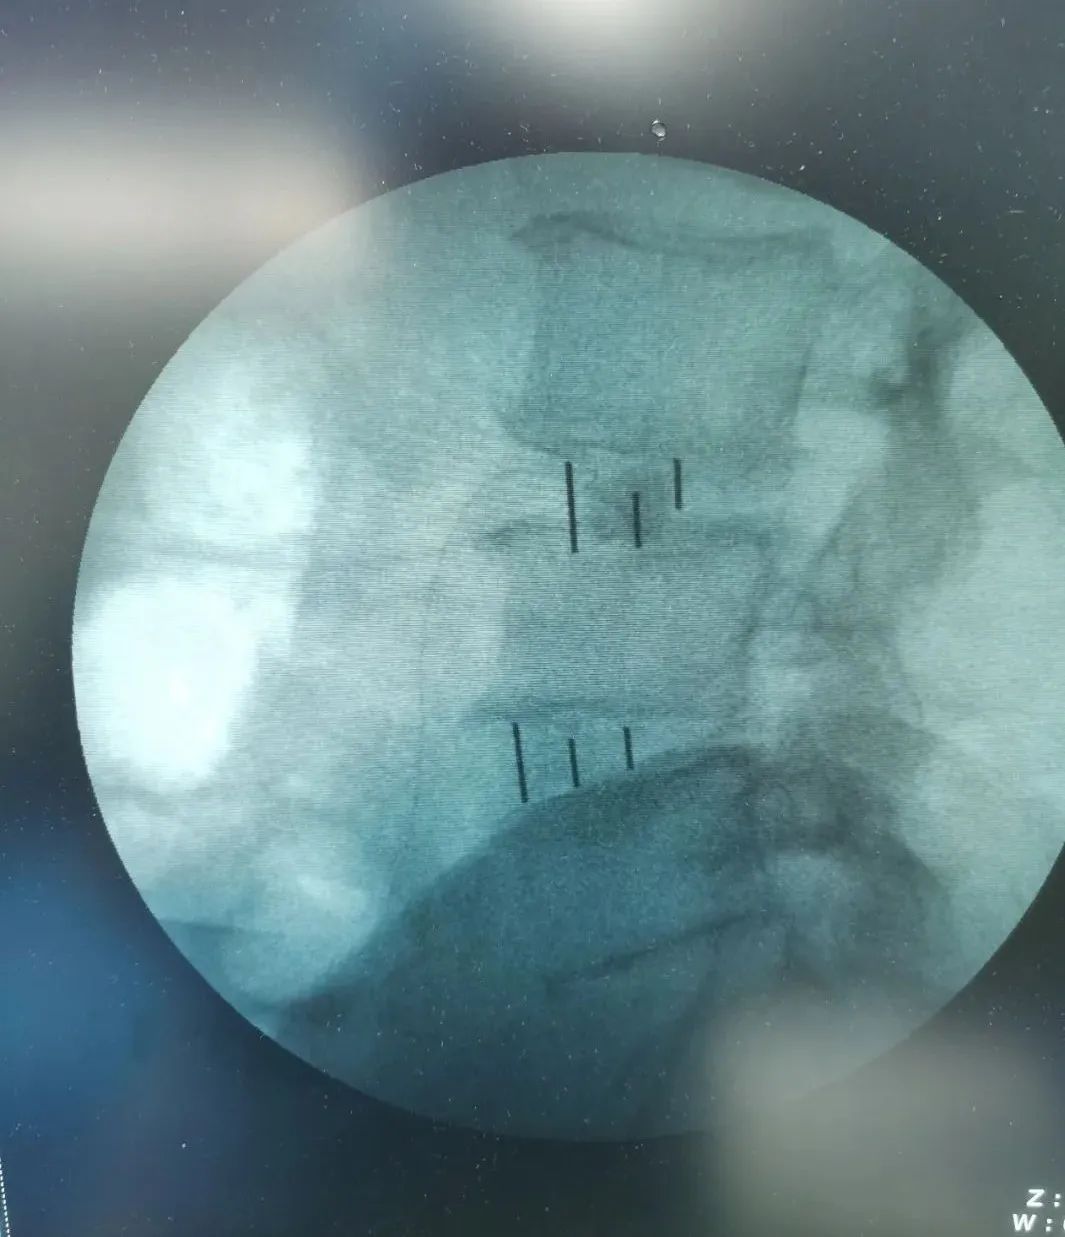

▲标记

▲术中影像

经过周密细致地术前讨论及评估,由张少华主任主刀,熊东医生、手术室(麻醉科)默契配合,为李先生成功实施“OLIF腰椎微创椎体间融合术”,目的:减压,复位,融合;术中操作干净利落、精准微创,顺利完成,手术历时近4小时。